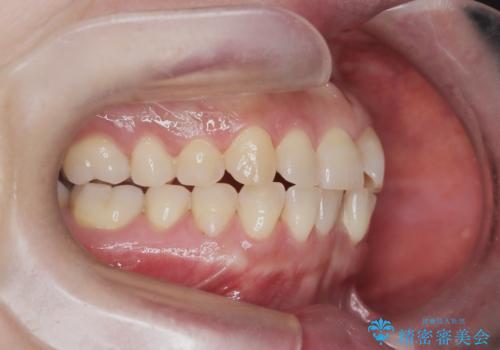

スペース確保のために、まず奥歯全体をわずかに後方へ動かす遠心移動を実施し、前歯を並べるためのスペースを確保。さらに、安全性に配慮しながら歯の側面をわずかに削るIPRを併用し、デコボコを解消しました。

ワイヤー矯正ならではの確実な歯のコントロールにより、当初の計画通り約1年という短い期間で、前歯のガタつきが解消。見た目が美しく整っただけでなく、清掃しやすい機能的な歯並びを獲得していただけました。